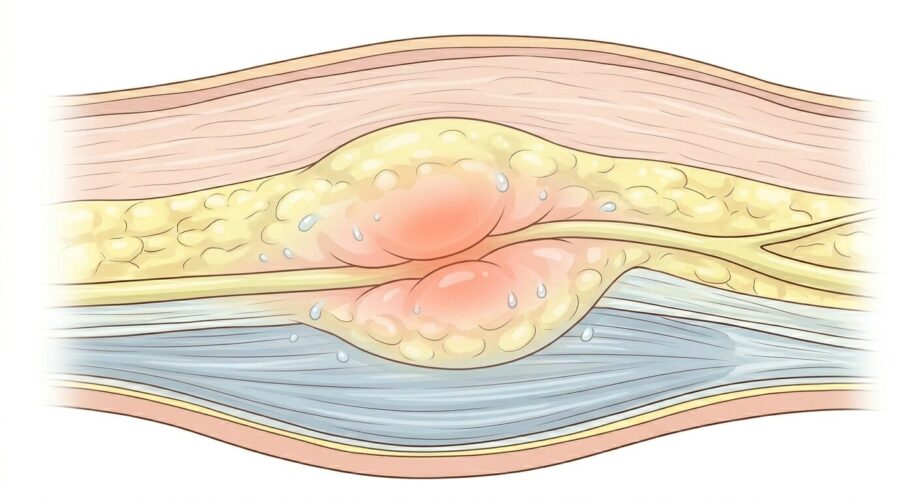

坐骨神経が絞扼(負担)を受けやすい理由③ 皮膚や皮下組織の滑りの問題

こちらは、筋肉の問題と近しい所はあるのですが、筋肉より浅い所には、皮膚や皮下組織と呼ばれる組織があります。

表面が突っ張った位で、坐骨神経には関係がなさそうですが、ジャストサイズより小さい革ジャンを着ている自分を想像してみてください。

人間の皮膚や皮下組織は通常はたわみがあり、身体を動かす際には、適当に前後左右に滑りながら動いています。

しかし、長期間悪い姿勢でいたり、仕事やスポーツなどで負荷をかけ続けると次第に滑りが悪くなってしまいます。

その結果、癒着と言って組織同士が張り付いた状態が起こり、坐骨神経の滑りも止めてしまいます。(ちなみに神経も通常は周りの組織の間を滑走し動いています)

結果的に神経に圧迫や牽引が加わり、痛みを起こします。

また、炎症が続くと先ほどお話しした皮下組織やファシアと呼ばれる組織が繊維化すると言われています。

繊維化すると言う事は、結果的には滑りが悪くなり、滑走障害が起こって、痛みやしびれの原因となります。